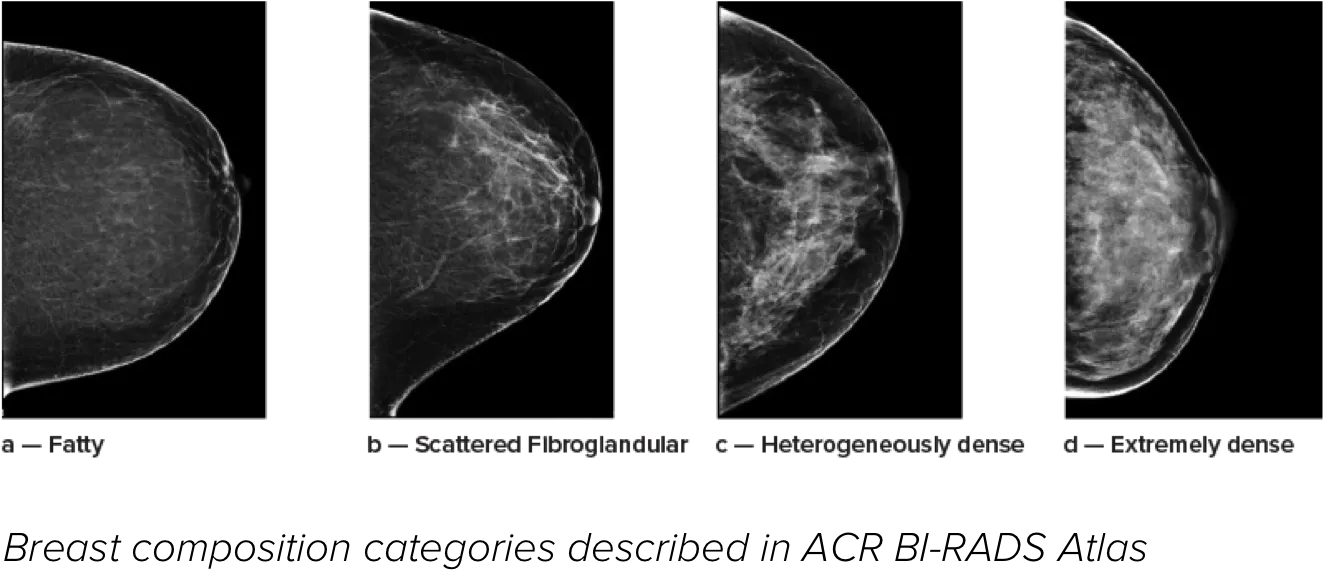

Higher breast density is known to increase a woman’s risk for breast cancer.1 The need for accurate, unbiased analysis is therefore critical. Powered by machine learning, Quantra technology software analyses both 2D™ and tomosynthesis images for distribution and texture of parenchymal tissue. It categorizes breasts in four breast composition categories consistent with guidance from the American College of Radiology (ACR) BI-RADS Atlas 5th Edition.2

Objective machine learning algorithm that assigns breast density category based on analysis of breast tissue texture and patterns.

*Scores are based on ACR BI-RADS categories, in line with the revised guidance by the American College of Radiation (ACR) BI-RADS Atlas 5th Edition. This accounts for pattern and texture, compared with volume, when determining density.

8. Breast composition categories as described in ACR BI-RADS Atlas.